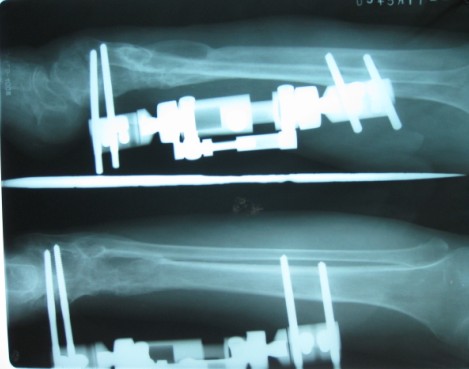

术后七年 骨不连

骨瓣移植术后